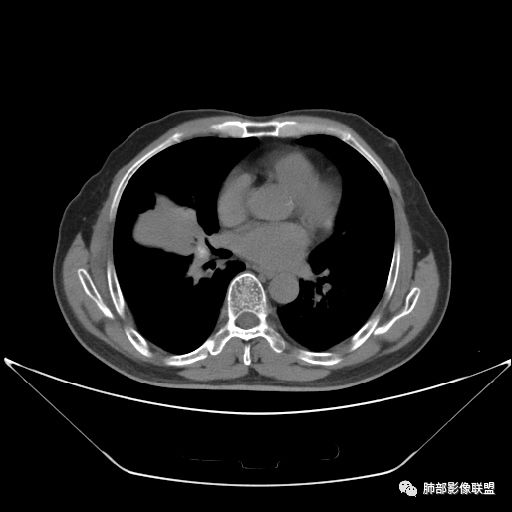

入院CT

老年男性,因“咳嗽咳痰1月余。”入院。病程中咳嗽咳痰,咳黄白痰,间断咯少许鲜红色痰血。PPD阳性。胸CT:右肺中叶外侧段支气管管腔阻塞,大片实性病变,病灶边缘光滑,部分边缘膨隆,可见分叶,肺门及纵隔可见肿大淋巴结,并可见钙化。增强可见病灶明显强化,而且延迟强化明显,病灶内多发低密度区,内见血管影,血管变细、部分血管破坏。考虑恶性病变可能性大,鉴别慢性肉芽肿性病变。

右肺中叶外侧段管腔阻塞、实性病变,病灶边缘光滑,可见分叶,肺门及纵隔可见肿大淋巴结,并可见钙化。增强可见病灶内多发低密度区。

老年男性,咳嗽、咳痰1月余,间断血痰。PPD阳性。

胸CT:跨叶大肿块,主体在中叶,右中叶外侧段支气管阻塞,病灶部分边缘膨隆,可见分叶,部分边缘平直,肺门及纵隔可见肿大淋巴结。增强病灶不均匀强化,延迟强化明显,病灶内多发低密度区,内见血管飘浮,部分血管变细、模糊。考虑:恶性病变可能性大,大细胞?淋巴瘤?鉴别慢性肉芽肿性病变。